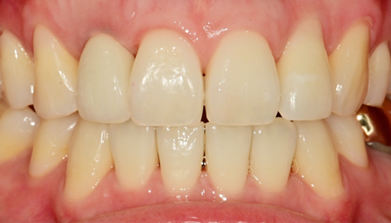

Final Implant Results

BEFORE/AFTER

AFTER

After 2 months, replaced with final prosthesis if gingival contour changes or as needed

After 2 months, if gingival contour changes

or as needed, replaced with final prosthesis